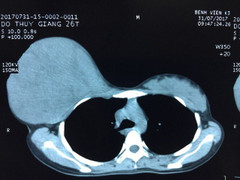

Dù có khối u với đường kính 20cm, nặng gần 3kg trong lồng ngực nhưng người đàn ông không hề hay biết.